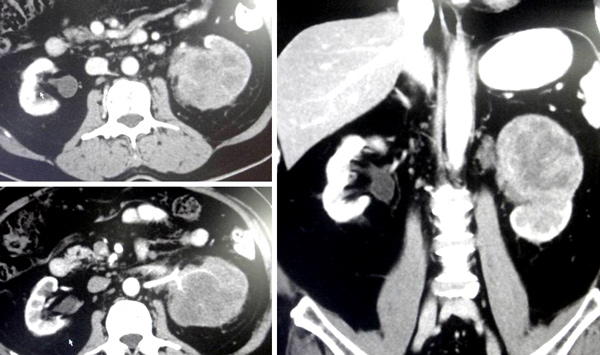

A CT scan on 30 October 2013 showed:

- Liver shows a least 7 hypodense lesions, largest 30 x 32 mm in the left lobe – likely metastases.

- Multiple enlarged lymph nodes in the celiac and paracaval regions.

- Sclerotic lesions at vertebral bodies of L3, L4 and L5 – likely metastases.